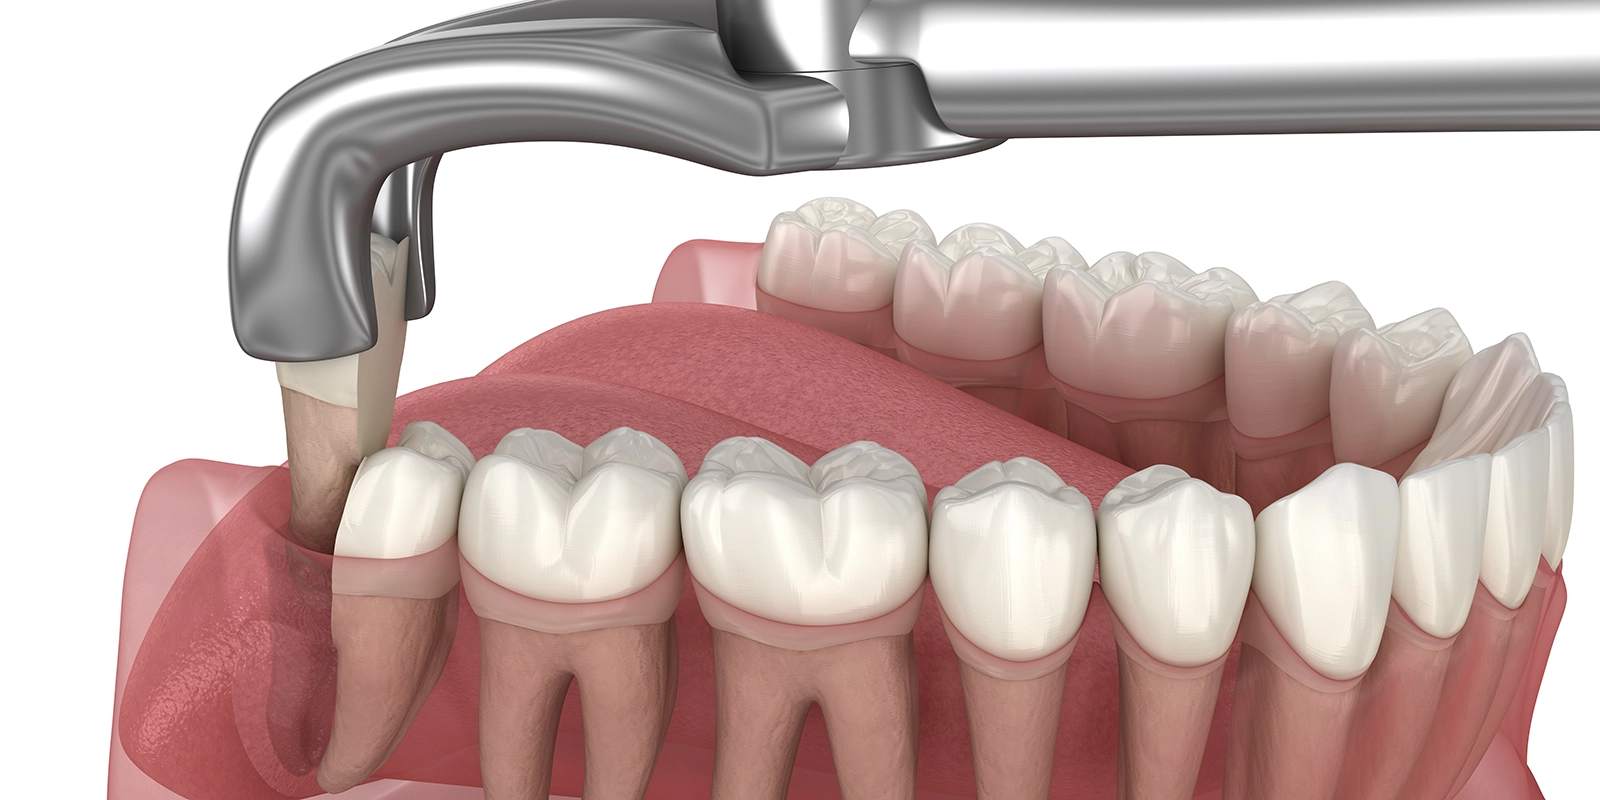

正常に生えている親知らずの抜歯は「単純抜歯」と呼ばれ、通常の抜歯と同じ手順で行います。麻酔をした後、特殊な器具で歯を挟んで揺らしながら抜きます。処置時間は10〜20分程度で、比較的簡単です。

一方、埋まっていたり、横向きに生えていたりする親知らずの抜歯は「外科的抜歯」となり、手順が複雑になります。まず麻酔をした後、歯茎を切開して骨を露出させます。親知らずを覆っている骨を削り、親知らずを確認します。親知らずが大きくて取り出せない場合は、歯を分割して数個に分けて取り出します。親知らず全体を取り出した後、傷口を縫合します。

外科的抜歯の処置時間は、30分〜1時間程度かかることもあります。複雑な症例では、より時間がかかることもあります。